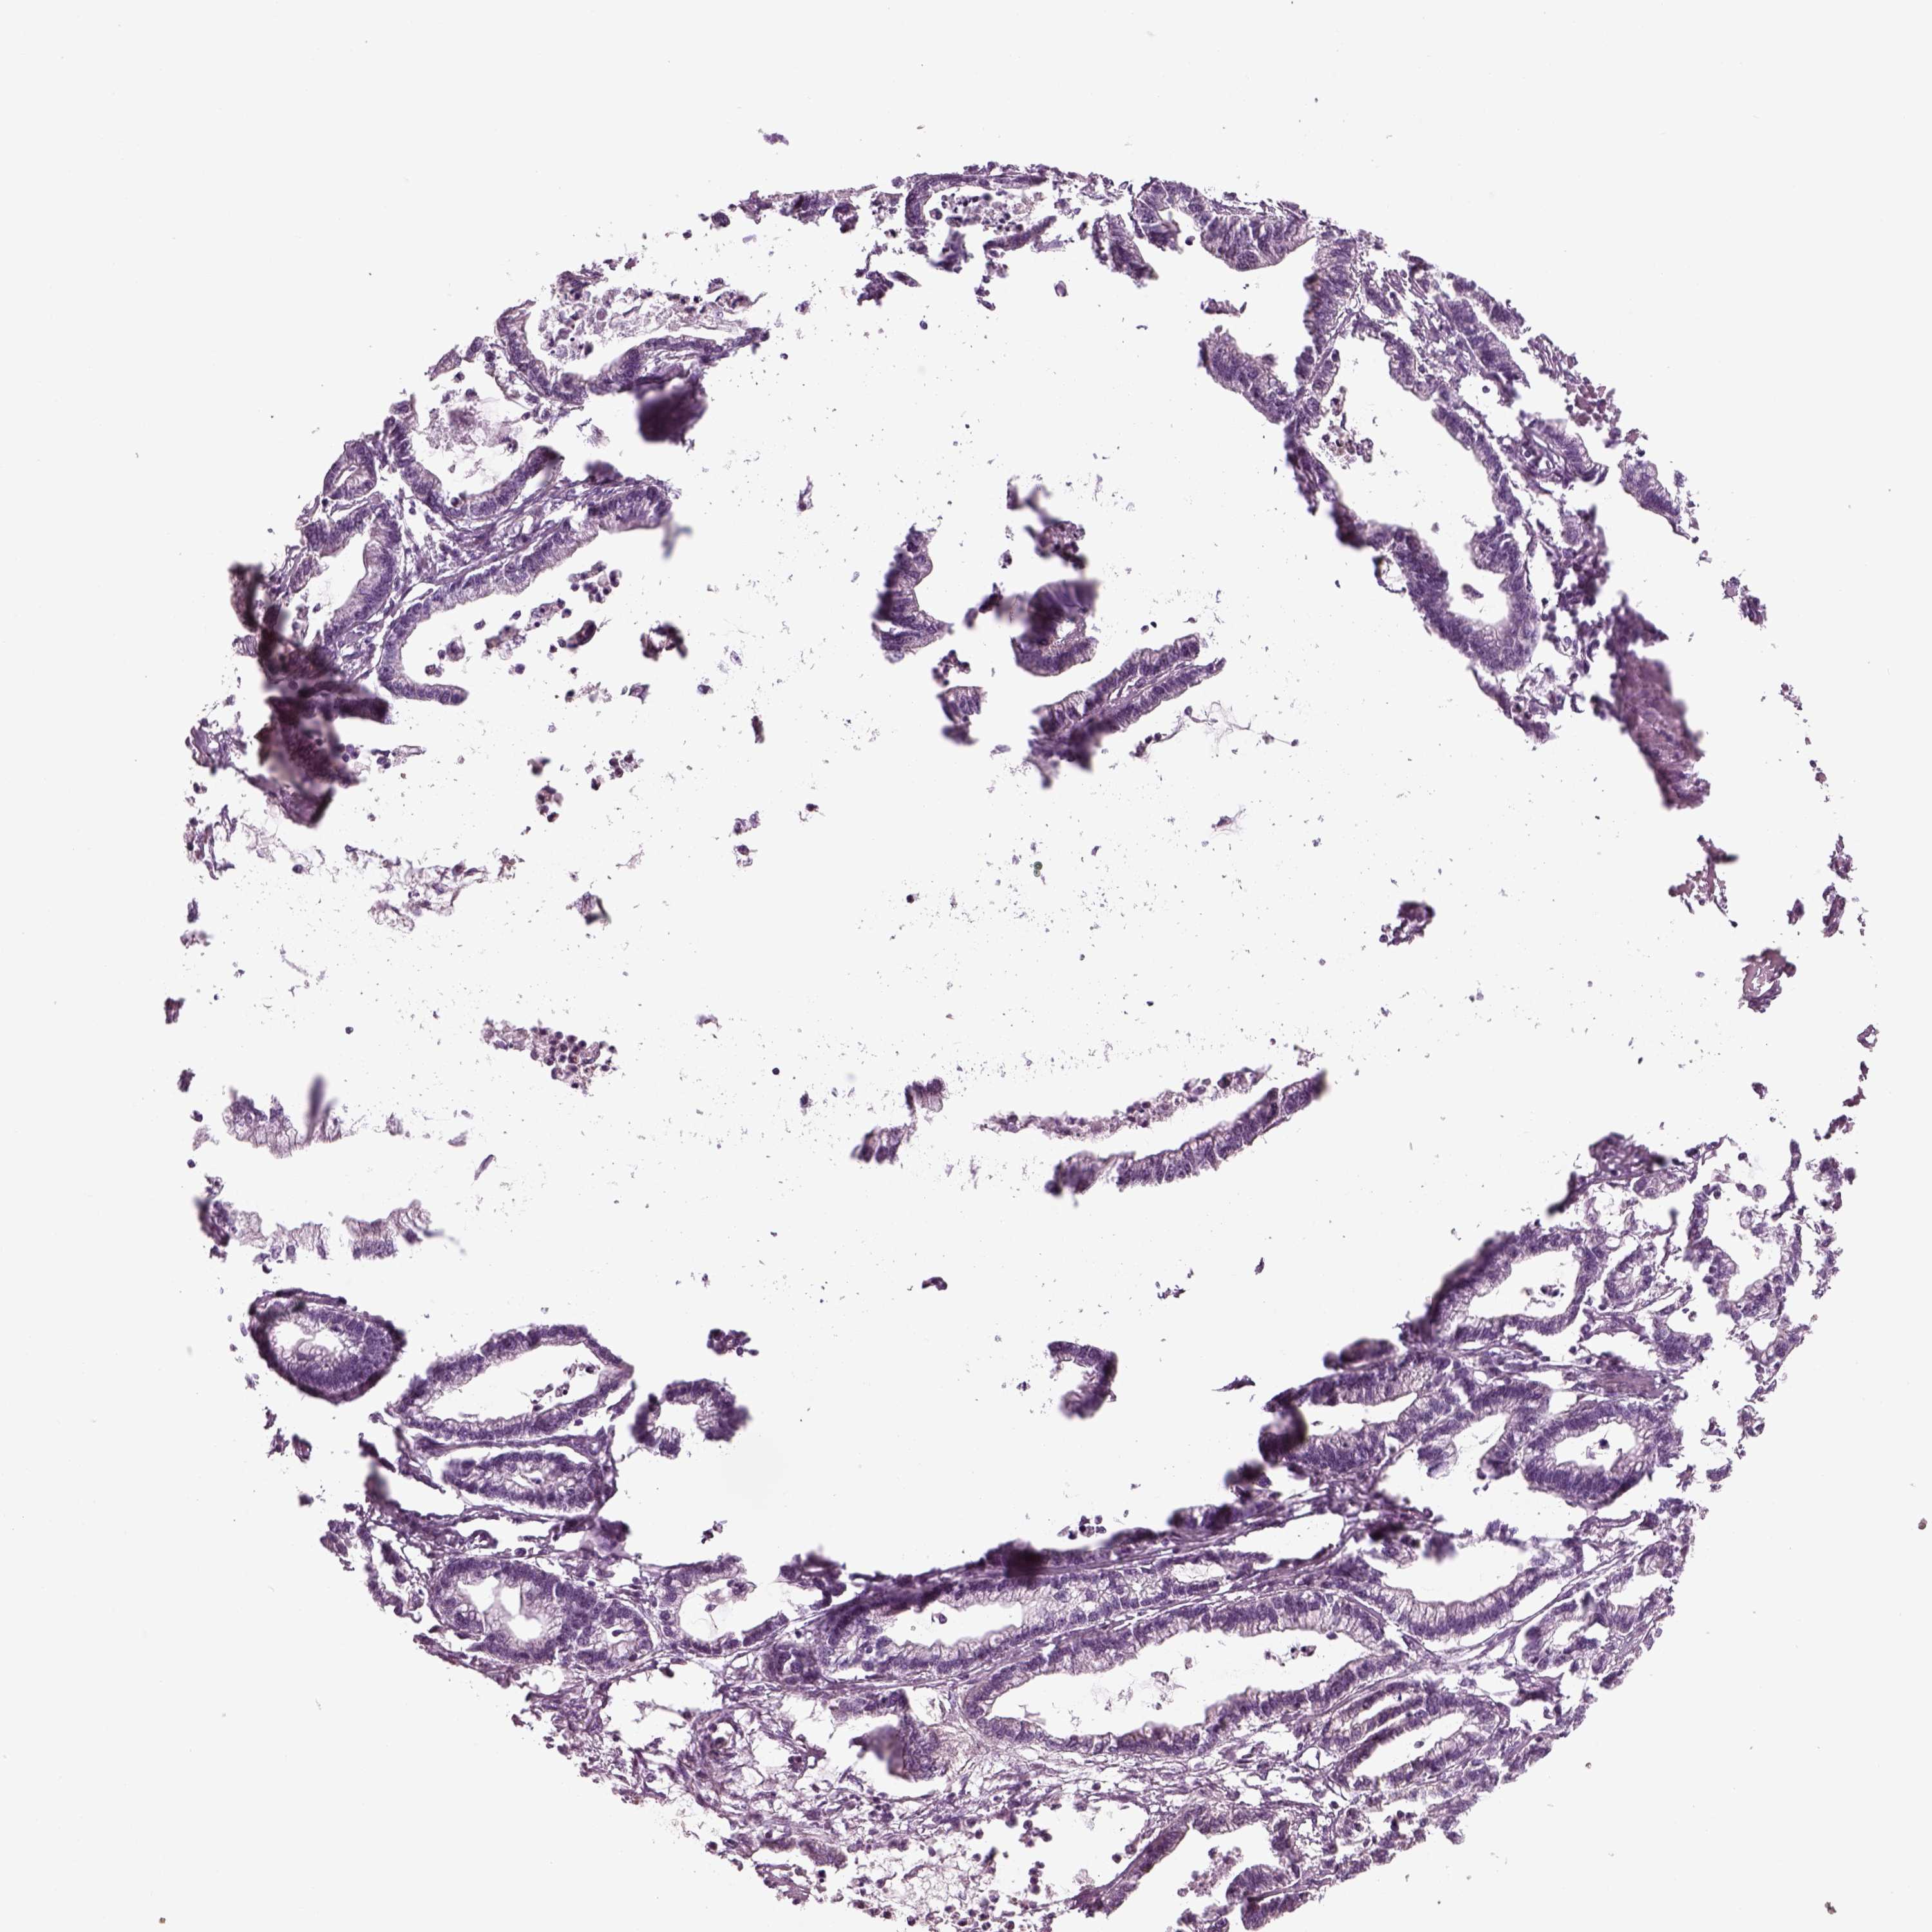

STOMACH CANCER - Protein expressioni

A mouse-over function shows sample information and annotation data. Click on an image to view it in a full screen mode. Samples can be filtered based on level of antibody staining by selecting one or several of the following categories: high, medium, low and not detected. The assay and annotation is described here.

Note that samples used for immunohistochemistry by the Human Protein Atlas do not correspond to samples in the TCGA dataset.

Antibody stainingi

Antibody staining in the annotated cell types in the current human tissue is reported as not detected, low, medium, or high, based on conventional immunohistochemistry profiling in selected tissues. This score is based on the combination of the staining intensity and fraction of stained cells.

Each image is clickable and will lead to virtual microscopy that enables deeper exploration of all samples and also displays staining intensity scores, fraction scores and subcellular localization as well as patient and tissue information for each sample.

Staining

High

Medium

Low

Not detected

Intensity

Strong

Moderate

Weak

Negative

Quantity

>75%

75%-25%

<25%

None

Location

Nuclear

Cytoplasmic/membranous

Cytoplasmic/membranous,nuclear

Adenocarcinoma, NOS

Adenocarcinoma, High grade